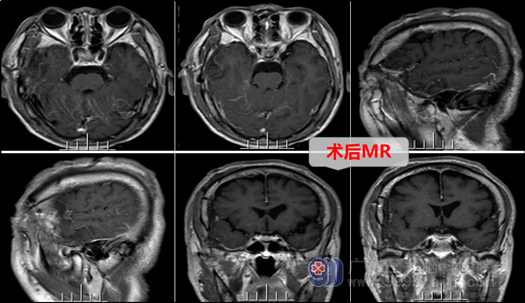

术前诊断:右侧颞部(颅中窝)占位:脑膜瘤。由于患者年龄大,心血管功能和肝肾功能都不太好,故手术医生和麻醉医生都非常重视。外十科团队在全麻下实施了“右侧颞部脑膜瘤切除术”,医生尽量加快手术,不让手术和麻醉时间过长。术中见肿瘤呈灰白色,质中,边界清楚,医生在显微镜下先分离肿瘤基底部,切断血供,然后很快完整摘除了肿瘤。术后患者神志清醒,无后遗症,安返监护室继续接受术后治疗。